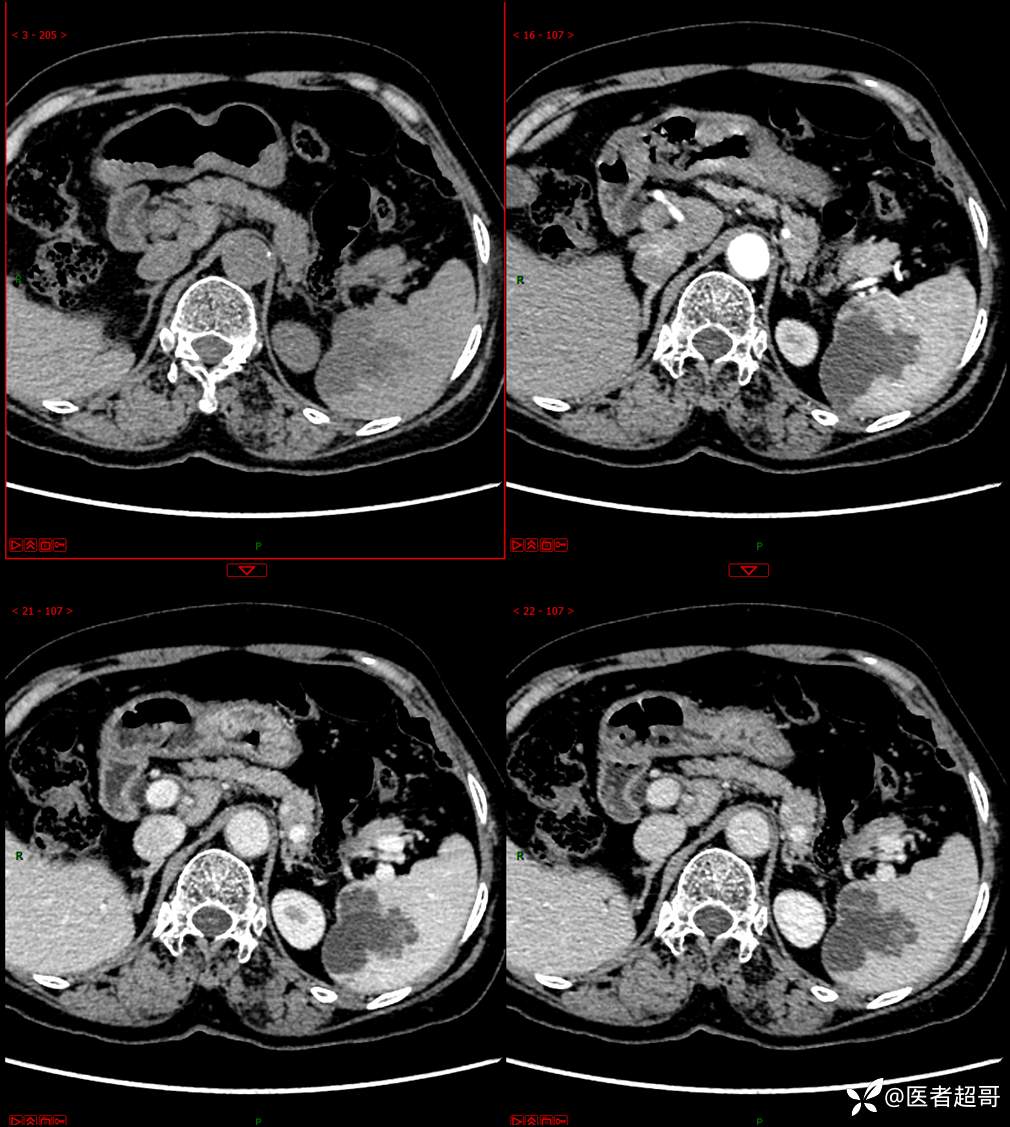

现病史:患者9天前于市人民医院查体时发现脾脏肿物,未行处理,后于我院门诊查,上腹部CT平扫+强化:脾脏占位,考虑良性,囊肿?脉管源性病变?患者诉平素无异常不适。现患者为求进一步诊疗,门诊遂以“脾肿物”收入院。患者自患病以来,神志清,精神可,饮食、睡眠可,大小便正常,体重未见明显变化。